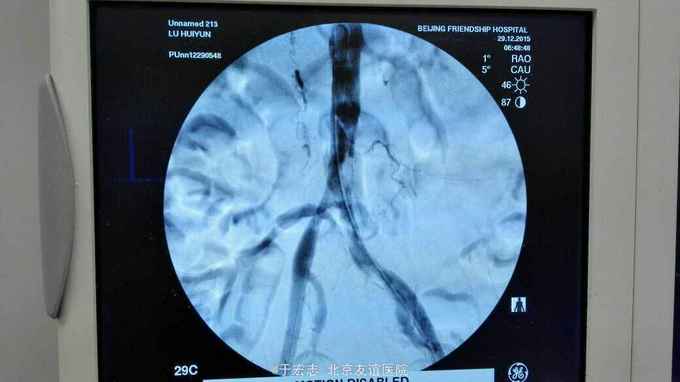

男性76岁,腹主动脉骑跨栓塞,经外院ct证实,病程3天,转至我院。

查体,双下肢大片皮肤青紫,双小腿无感觉,双股动脉波动消失

全腔内技术操作,用8F rotarex机械取栓导管操作,术前留置股静脉鞘,边操作边放静脉血,减少毒素吸收。静脉血经自体血回收处理。 操作完成后以血管缝合器缝合股动脉穿刺点,加压包扎。 患者转重症医学科途中出现心跳骤停,于手术室心外按压2小时复苏成功,转重症医学科血滤治疗。术后五小时生命体征均可维持,但家属还是放弃进一步治疗转运回当地治疗。